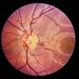

- Vascular Loops

- vascular loop

- Color photo showing corkscrew loop on right optic nerve.